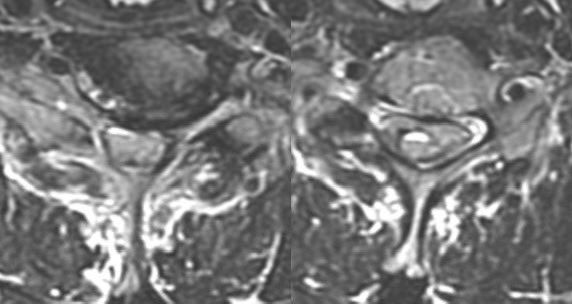

What is the most likely diagnosis in this 65 y/o M presenting w/ leg weakness, hyperreflexia, spasticity and absent vibration sense in the LE? #neu